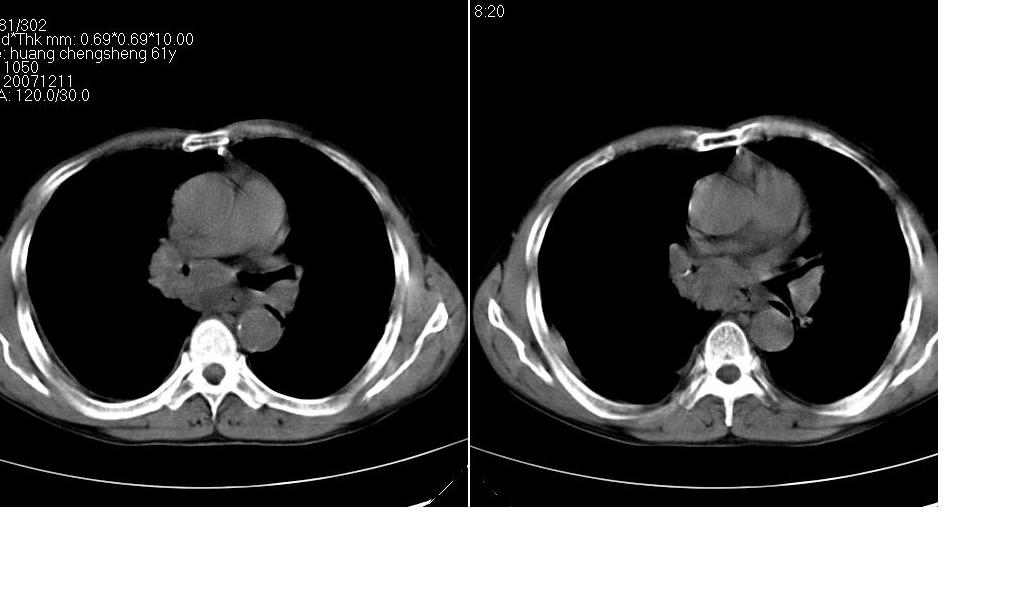

考虑:1、右肺下叶中心型肺癌并纵隔淋巴结转移。胸腔积液。

2、心包少量积液。

3、左肺改变不除外癌性淋巴管炎或化疗后肺间质纤维化。

纵隔及右肺门淋巴结肿转移,右肺改变是否为阻塞性肺气肿改变?左肺改变支持淋巴管炎的诊断;化疗后肺改变应该双肺都有改变。

1 右肺下叶中心型肺癌.纵隔内淋巴结转移.右侧胸腔积液. 2 心包少量积液.3 肺间性改变考虑与化疗有关.

补充一下:右肺底好象有一个类圆形的结节影,可考虑为肺部转移。如图示。[